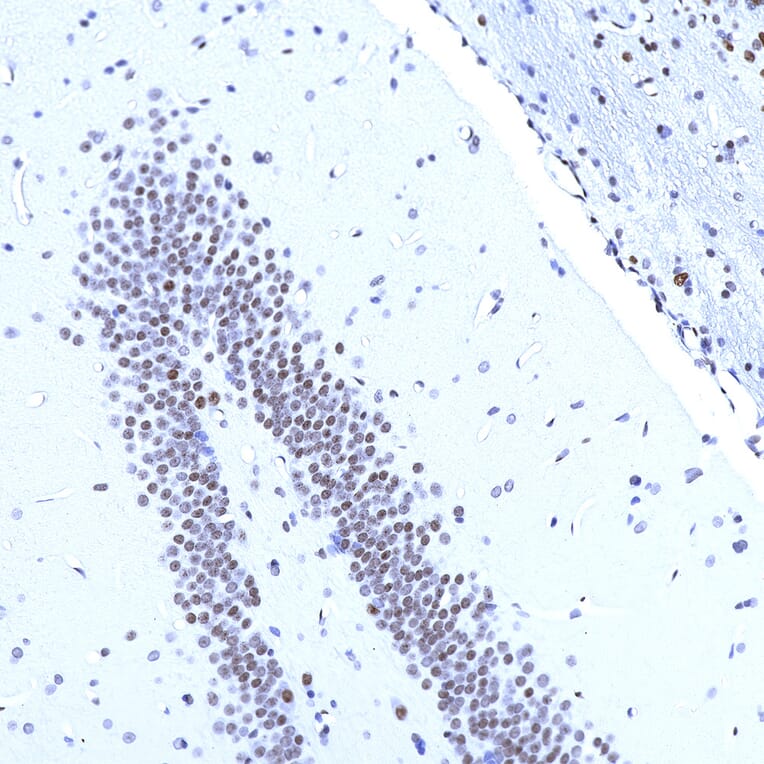

Immunohistochemistry analysis of a 4% PFA fixed paraffin embedded rat hippocampus section with Anti-MeCP2 Antibody [4F11] (A104324) at a dilution of 1:1,000 detected with DAB (brown) using the Vector Elite ABC-HRP detection and reagents with citra buffer retrieval. Counterstained with Hematoxylin (blue). Anti-MeCP2 Antibody [4F11] (A104324) labels the nuclei of neurons with varying degree of expression. Note: this antibody performs well in testing with 4% PFA fixed tissues but does not stain NBF fixed tissue effectively.